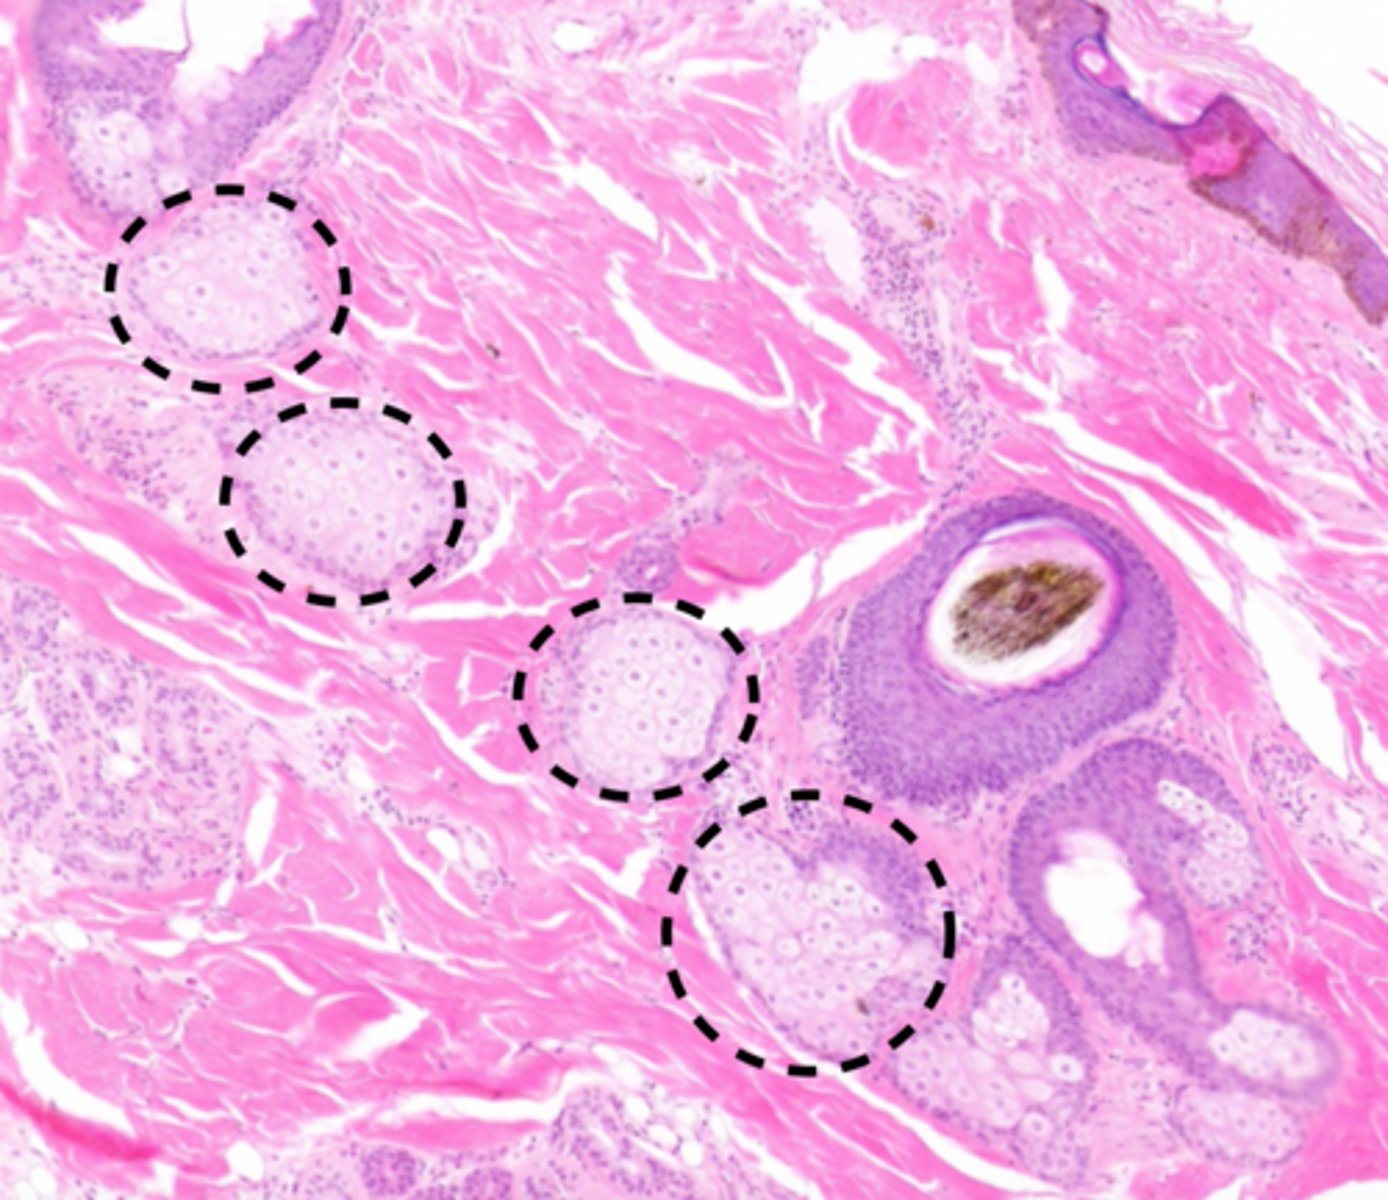

dermal adnexa

- hair/feather follicles

- sebaceous gland

- apocrine gland

hair/feather follicle

a small tubular cavity containing the root of a hair

3 parts of the hair follicle

bulb (where growth starts)

root

shaft

simple hair follicle

- where a single hair emerges from a singular orifice

sebaceous glands

secrete sebum (oil) into the hair follicles where the hair shafts pass through the dermis

sebocytes

Cells that produce sebum in sebaceous glands.

rupture to release sebum

apocrine glands

Coiled structures attached to hair follicles found in the underarm and genital areas that secrete sweat.